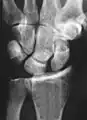

Dynamic scapholunate instability visible upon clenching the wrist

X-ray images indicate scapholunate ligament instability when the scapholunate distance is more than 3 mm, which is called scapholunate dissociation.[7] A static scapholunate instability is generally readily visible, but a dynamic scapholunate instability can only be seen radiographically in certain wrist positions or under certain loading conditions, such as when clenching the wrist, or loading the wrist in ulnar deviation.[6]

In order to diagnose a SLAC wrist you need a posterior anterior (PA) view X-ray, a lateral view X-ray and a fist view X-ray.[8] The fist X-ray is often made if there is no convincing Terry Thomas sign. A fist X-ray of a scapholunate ligament rupture will show a descending capitate bone. Making a fist will give pressure at the capitate, which will descend if there is a rupture in the scapholunate ligament.